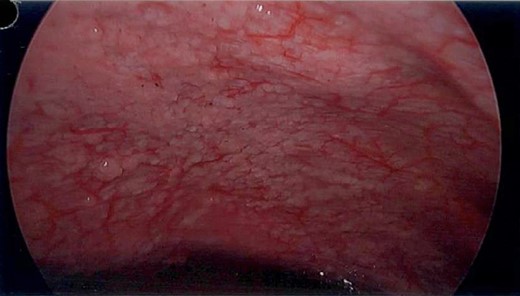

A 69-year-old otherwise well female with no prior history of malignancy underwent colonoscopy for investigation of upper abdominal pain, altered bowel habits—looser, more frequent stools—and subacute weight loss of 8 kg over a number of years. At colonoscopy, luminal narrowing, the impression of colonic thickening and very poor distension was encountered at the ascending colon (Fig. 1). The colonoscope was unable to traverse the narrowed segment. The remainder of the colon was unremarkable and there was no evidence of diverticulosis. Given the normal appearance of the mucosa at the area of presumed pathology, deep biopsies were taken using a bite-on-bite technique in order to ensure that submucosa was captured in the sample. Upper endoscopy was also performed and was normal.